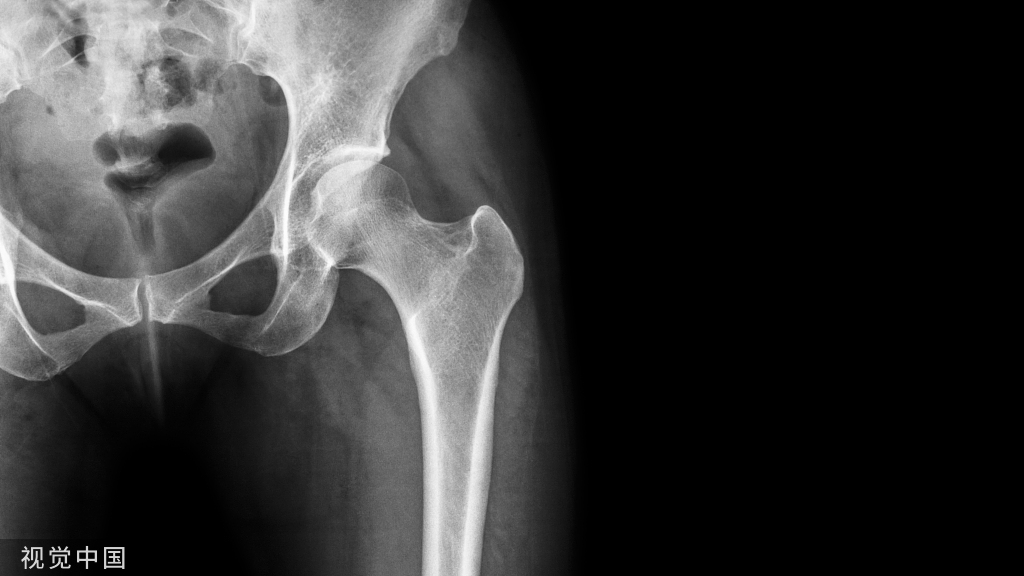

滑囊是关节囊外的囊性结构,可与关节囊相通,其作用是减少肌腱、骨和皮肤之间的摩擦。可以分为先天性滑囊和获得性滑囊。